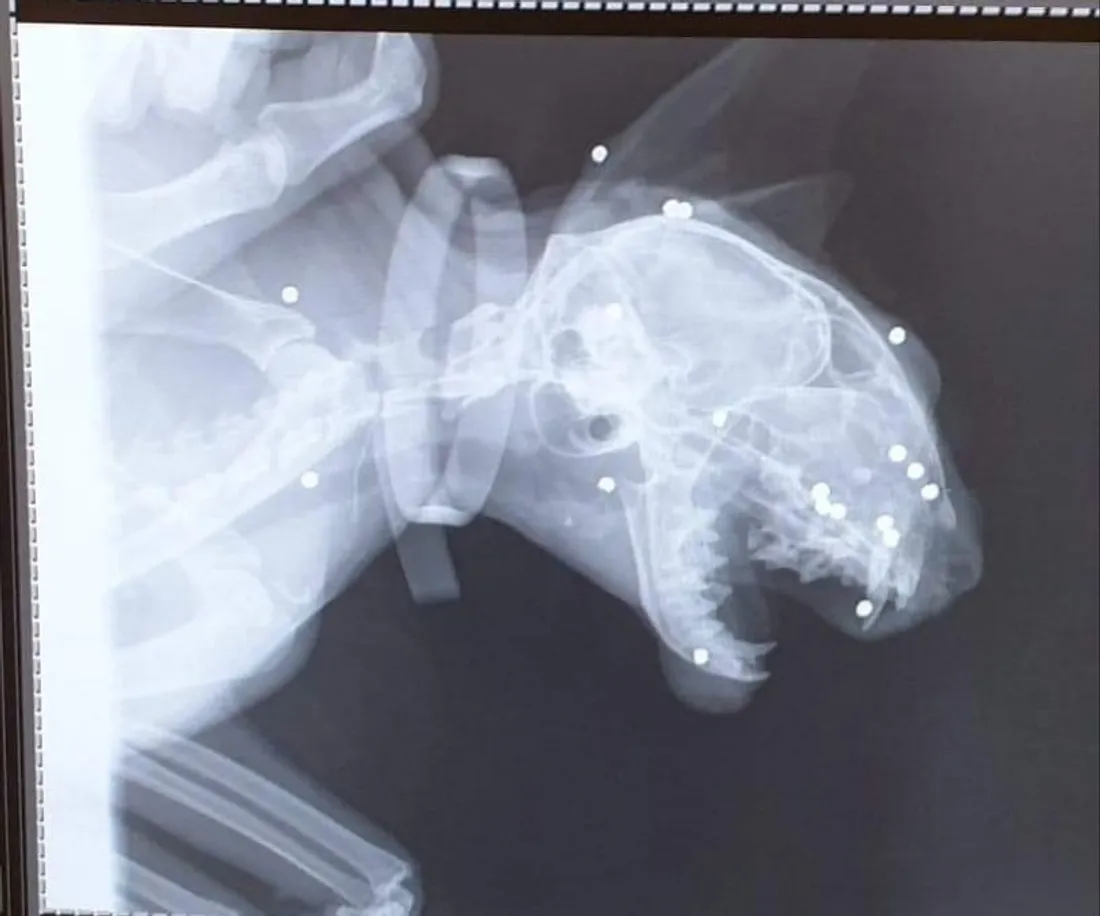

L'animal est devenu aveugle et a terriblement souffert suite à chacun de ces impacts.

Ce jour d'avril dernier, elle avait reçu 18 plombs dans la tête simplement parce qu’il s’était rendu dans le jardin du voisin.